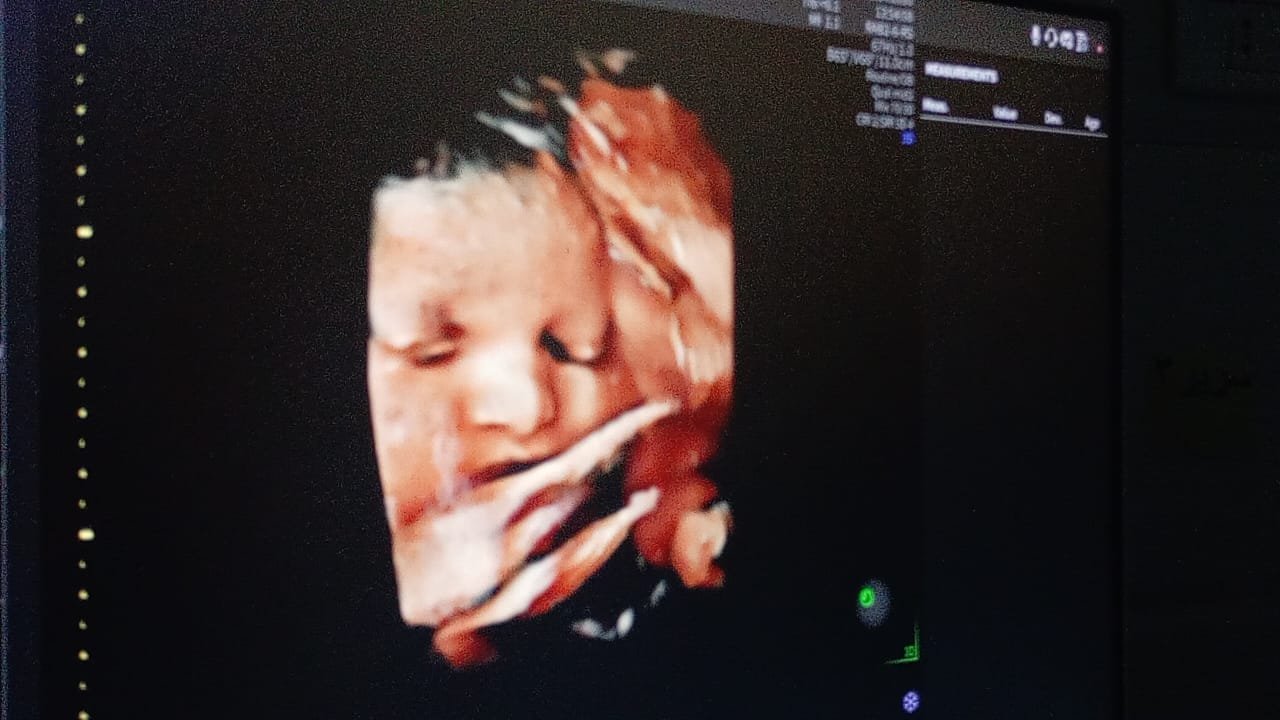

وأكد الدكتور أحمد البيلي وكيل وزارة الصحة، أن هذه الدورة تأتي في إطار خطة وزارة الصحة والسكان ومديرية الشئون الصحية لتطوير خدمات الأشعة، خاصة مع توريد أول جهاز سونار رباعي الأبعاد بمستشفى الزقازيق العام، والذي سيتم تشغيله فور الإنتهاء من الدورة التدريبية، بما يساهم في تحسين دقة التشخيص ورفع كفاءة الخدمات الطبية المقدمة للمرضى بمستشفى الزقازيق العام، مشيراً إلى أهمية التدريب العملي على أحدث الأجهزة والتقنيات الطبية.

وأشار الأستاذ محمود عبدالفتاح مدير الإعلام والعلاقات العامة بالمديرية، إلى أن التدريب تضمن محاضرات وورش عمل عن تقنيات السونار ثلاثي ورباعي الأبعاد، وآليات تحسين جودة الصورة ودقة التشخيص، وفحص حالات فعلية داخل قسم الأشعة، لرفع كفاءة أداء الأطباء في مجال تشخيص أمراض الأجنة، كما تم تدريب أطباء الأشعة وأطباء النساء والتوليد على الاستخدام الأمثل للتقنيات الحديثة، كما قدم وكيل الوزارة شهادات اجتياز الدورة التدريبية للمتدربين، لافتاً أن الفعاليات شملت تكريم رئيس وفريق مكافحة العدوى بمستشفى الزقازيق العام لحصولهم على المركز الأول على مستوى المحافظة بناء على تقييم الوزارة الفترة السابقة.